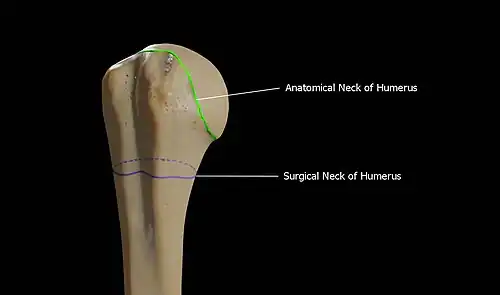

Head

The head (caput humeri) is nearly hemispherical in form. It is directed upward, medialward, and a little backward, and articulates with the glenoid cavity of the scapula to form the glenohumeral joint (shoulder joint). The circumference of its articular surface is slightly constricted and is termed the anatomical neck, in contradistinction to a constriction below the tubercles called the surgical neck which is frequently the seat of fracture. Fracture of the anatomical neck rarely occurs.[2] The diameter of the humeral head is generally larger in men than in women.

Anatomical neck

The anatomical neck (collum anatomicum) is obliquely directed, forming an obtuse angle with the body. It is most prominent in the lower half of its circumference, while in the upper half, it is represented by a narrow groove separating the head from the tubercles. The line separating the head from the rest of the upper end is called the anatomical neck. It affords attachment to the articular capsule of the shoulder-joint, and is perforated by numerous vascular foramens. Fracture of the anatomical neck rarely occurs.[2]

The anatomical neck of the humerus is an indentation distal to the head of the humerus on which the articular capsule attaches.

Surgical neck

The surgical neck is a narrow area distal to the tubercles that is a common site of fracture. It makes contact with the axillary nerve and the posterior humeral circumflex artery.